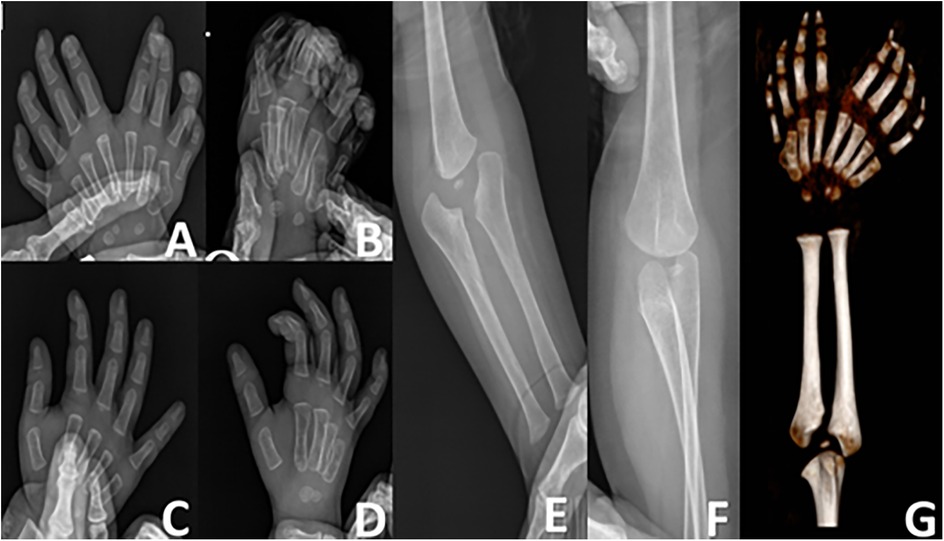

Abstract Congenital anomalies of the hand and forearm present a complex challenge in plastic and pediatric surgery. We present the case of a 13-month-old child with a congenital left mirror deformity, characterized by the presence of eight digits and two ulnae exhibiting near-perfect bilateral symmetry. A novel palmar-based incision design was employed for the corrective and functional reconstruction of the left hand,which may serve as a reference for the surgical management of similar conditions. Preoperatively, the radial-side middle finger demonstrated palmar opposition against the ulnar aspect of the palm.The surgical procedure included resection of the radial-sided index, ring, and little fingers , along with pollicization of the middle finger. Functional reconstruction of the neothumb involved restoring adduction and abduction using preserved native anatomical structures. Following comprehensive clinical and imaging evaluations, the patient underwent successful surgical treatment.Postoperatively, substantial improvements were observed in both hand morphology and grasping function. Through our novel palmar incision approach, we effectively reconstructed thumb opposition and adduction while preserving intrinsic hand musculature and achieving optimal scar concealment. In managing mirror hand deformities, meticulous selection of the most dominant digit for thumb reconstruction remains crucial. At the initial surgical stage, osteotomy of the selected digit was performed to enhance its morphological similarity to a normal thumb.